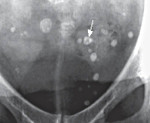

• Рентгенография таза. На обзорных фотографиях непроницаемые для крови пятна видны в виде овальных структур с концентрическими кольцами («пучками»). Наличие радиационно-прозрачного центра, являющегося симптомом хвоста кометы, считается важным диагностическим признаком тазовых камней.